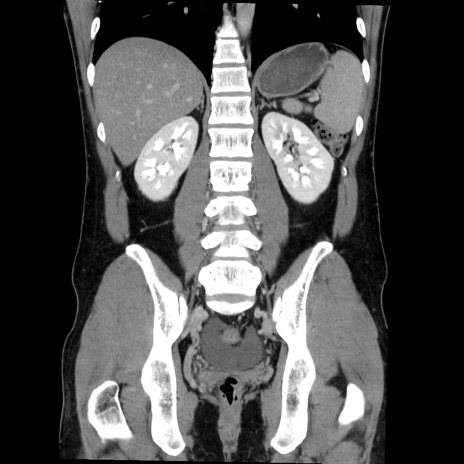

症例36(冠状断像)

【症例】20歳代 男性

【主訴】心窩部痛

【現病歴】今朝より上腹部痛あり。一旦軽快していたが再度出現したため救急要請。昨日夕に白身の魚を含む刺身を食べた。

【身体所見】BP 136/89mmHg、HR 74/min、BT 37.0℃、腹部:膨満、軟、心窩部に圧痛あり。反跳痛なし、筋性防御なし、腸雑音やや亢進あり。

【データ】WBC 17700、CRP 0.48